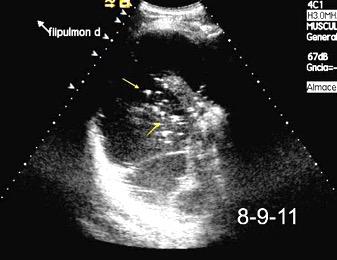

Patrón ecográfico de empiema

Anecoico.....0%. (0 de 47)

Complejo no septado no hiperecoico... ……………..0% (0 de 36)

Complejo, no septado hiperecoico......100% (2/2)

Complejo septado …35% (11 de 31)

Ecogénico homogéneo .... 100% (2 de 2)

Wang T et al. Value of ultrasonography in determining the nature of pleural effusion. Analysis of 582 cases. Medicine 2022.

Chih-Yen Tu et al. Chest Ultrasound Study Pleural Effusions in Febrile Medical ICU. Chest 2004